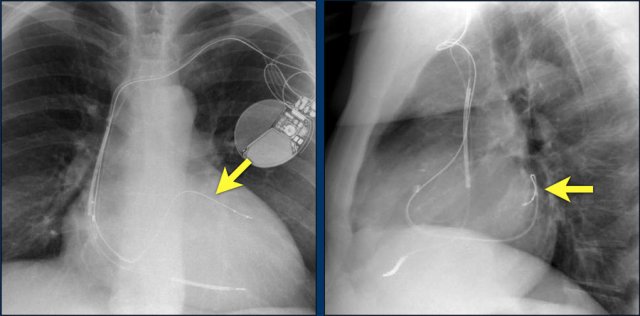

The image is taken immediately after placement of an ICD.

There is a small pneumothorax (arrow).

This is the most common complication.